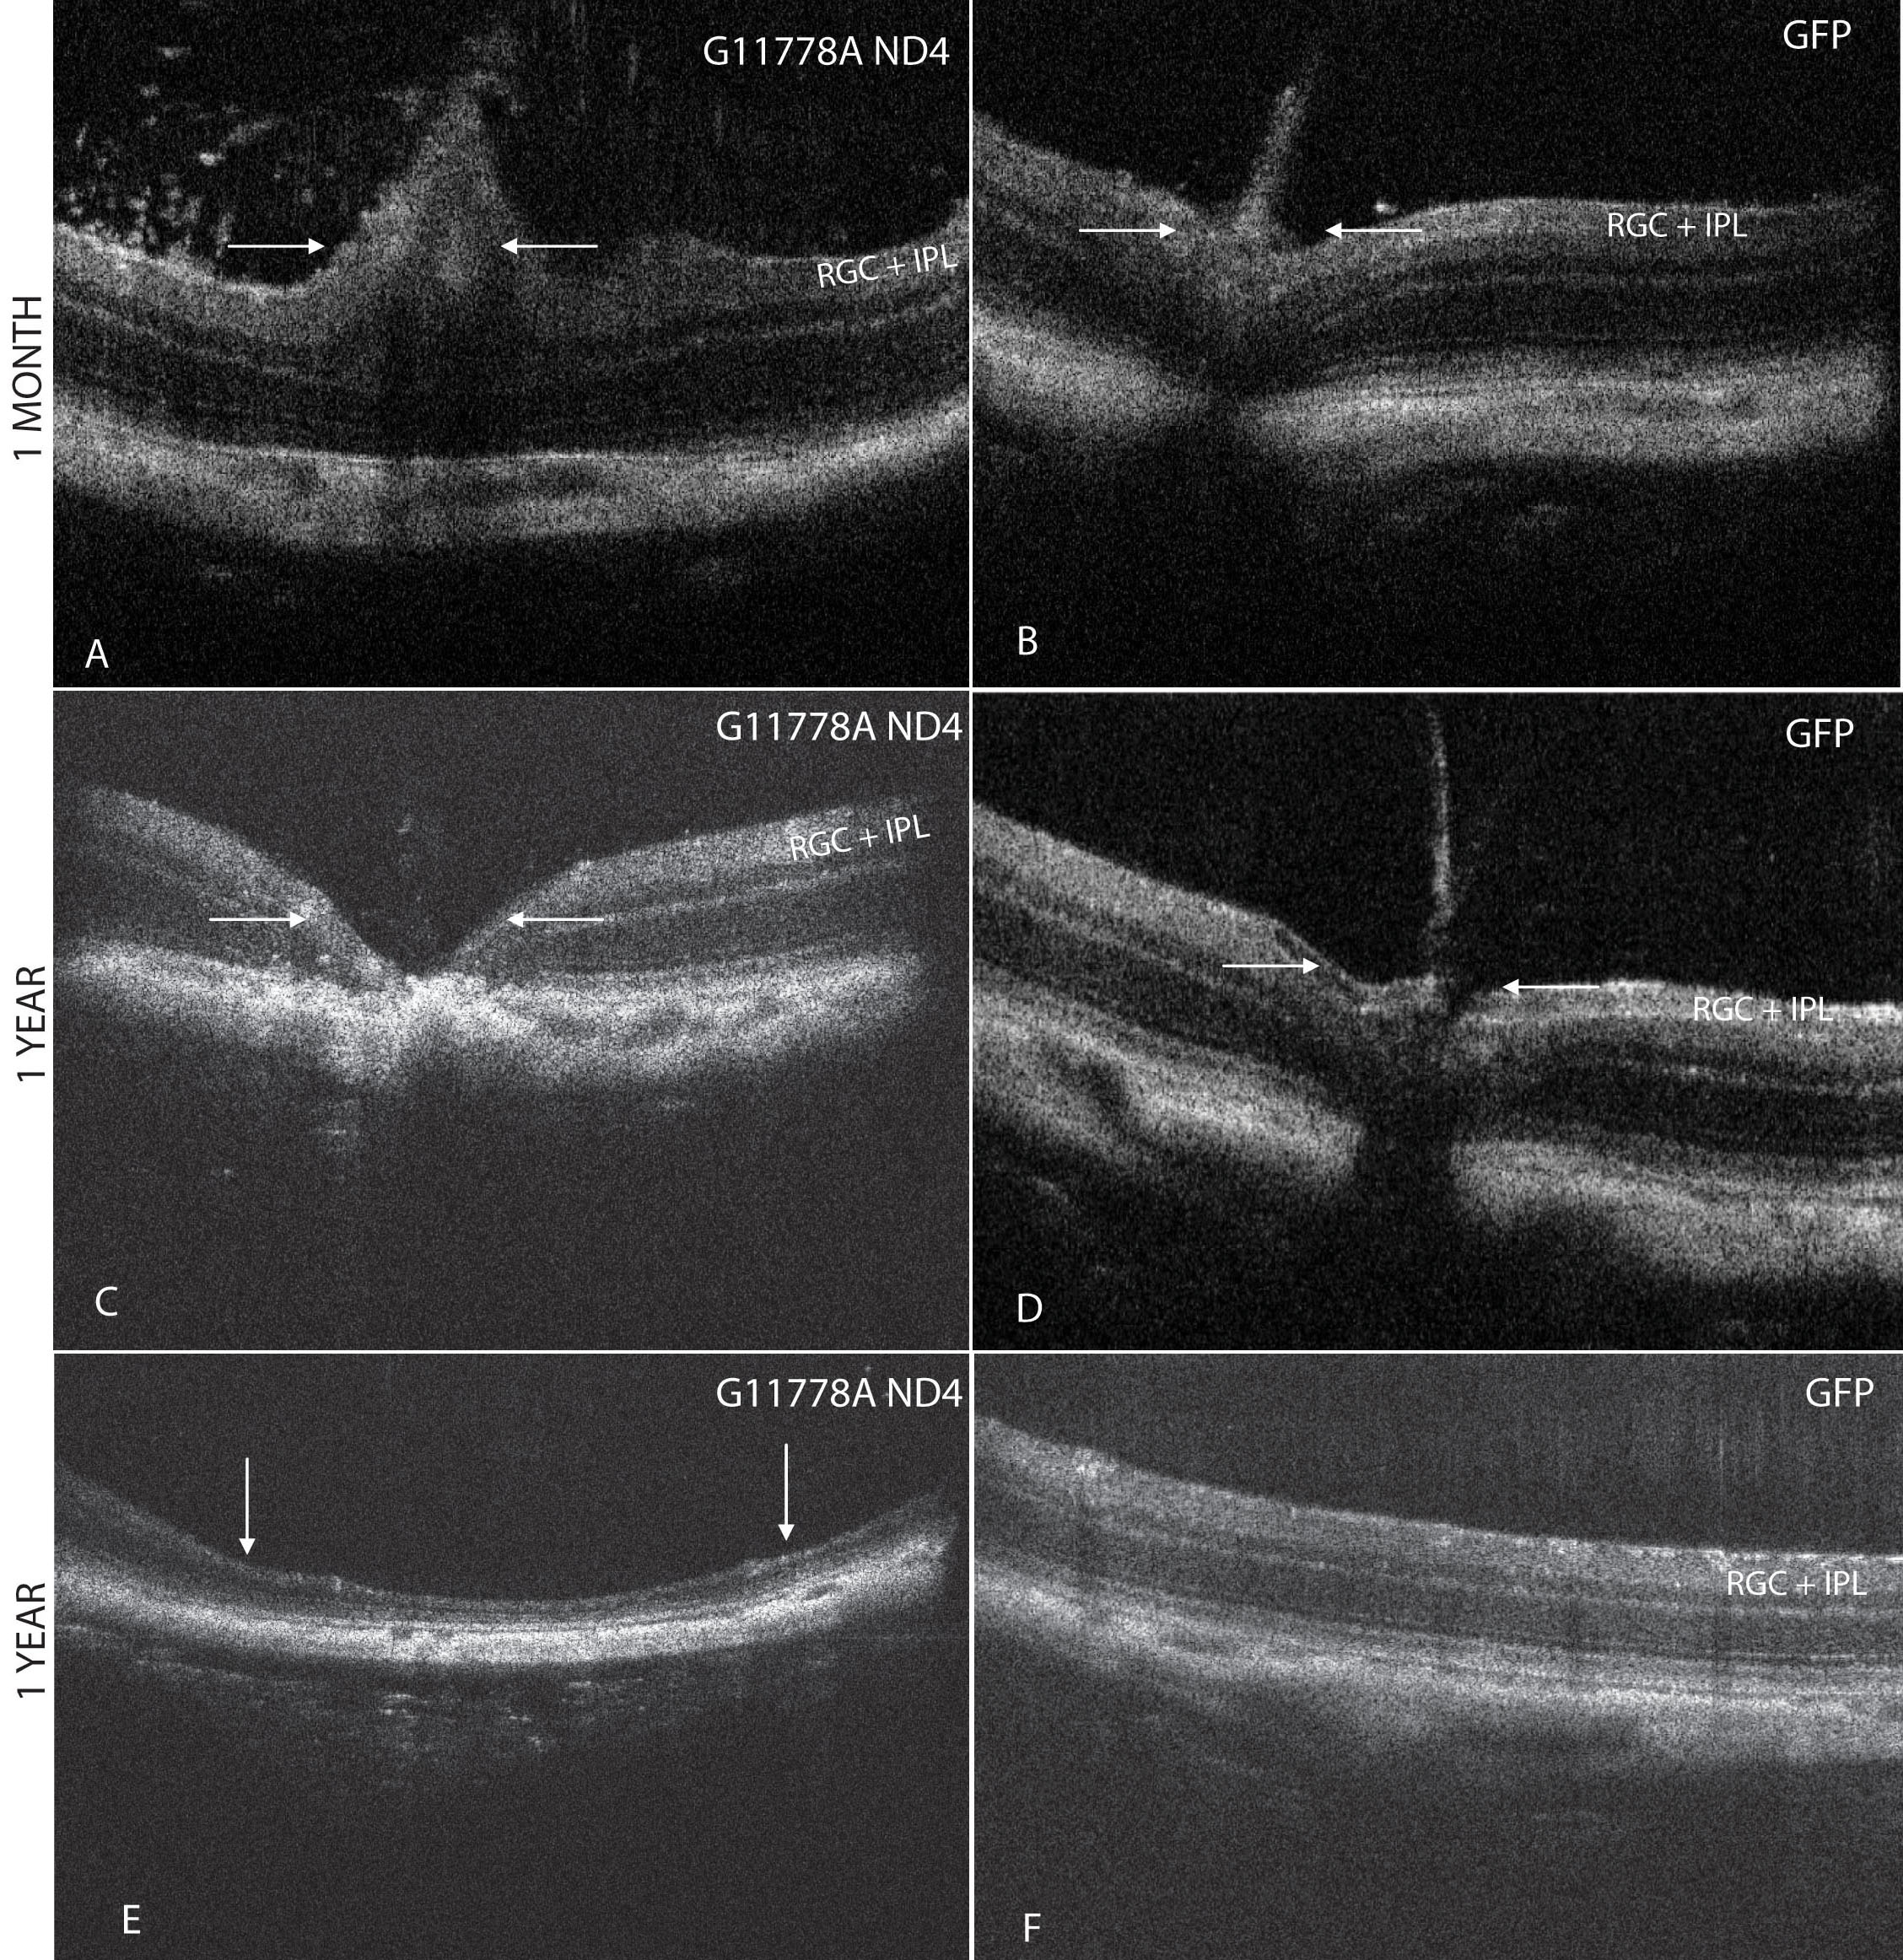

Figure 5. SD-OCT imaging of optic

disc edema and optic atrophy. A: Spectral domain optical

coherence tomography (SD-OCT) of right eyes injected with the

mutant human ND4 packaged with the MTS scAAV revealed

swelling of the optic nerve head (arrows) commencing at 1 month

post injection. A focal increase in the thickness of the RGC and

the inner plexiform layer (IPL) is apparent just to the right of

the swollen optic nerve head. B: The control eye

injected with scAAV-GFP showed the normal anatomy of the mouse

optic nerve head. C: One year post injection, optic

nerve head atrophy was apparent in the mutant ND4 injected eyes.

D: The contralateral GFP injected control eyes maintained

normal optic nerve head anatomy. E: One year post

injection, focal thinning with loss of the inner retina was also

apparent in an experimental eye, but this finding was not seen

in any of the control eyes (F). RGC=retinal ganglion cell

layer; IPL=inner plexiform layer.